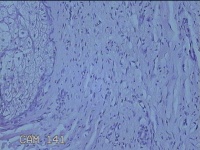

左侧眼眉部结节

性别

男

年龄

51岁

临床诊断

皮下结节

一般病史

发现左侧眼眉部结节2年余。

标本名称

大体所见

灰白暗红色结节0.8x0.7x0.2cm一个,表面糜烂,切开结节呈实性,切面灰白暗红色,质软。

图1